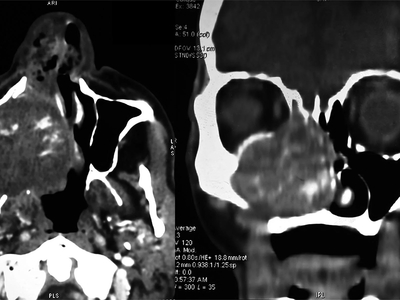

An “enormous” gossypiboma, which is a mass inside the body composed of retained surgical gauze or sponge surrounded by an inflammatory foreign body reaction.